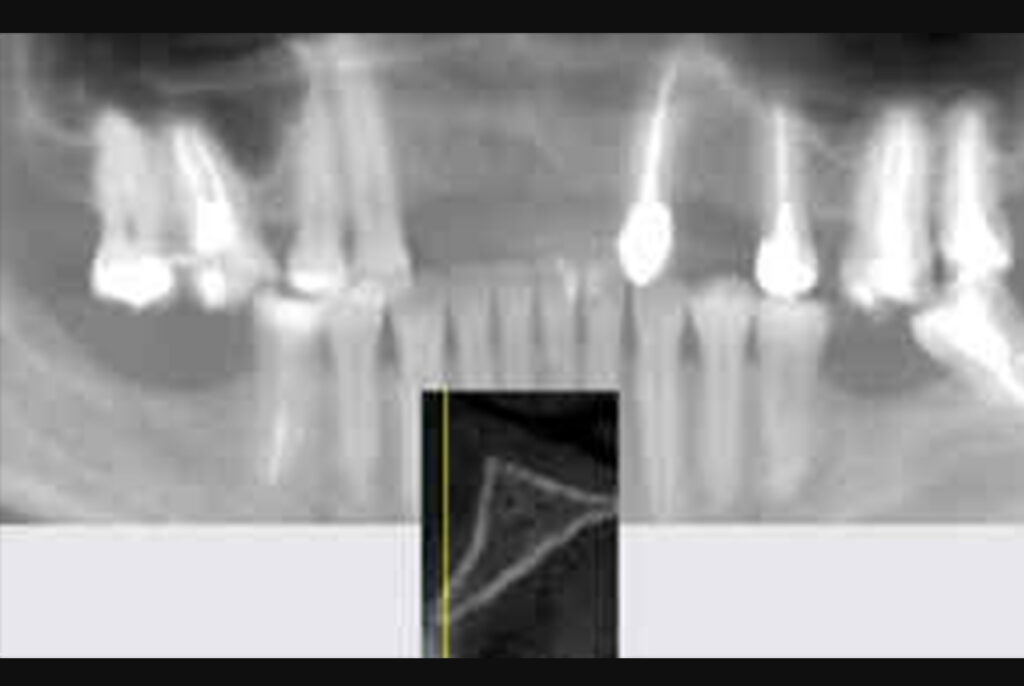

Computed tomography showed the presence of 3mm of remaining bone thickness, with medullary bone, and preservation of alveolar bone height (Figure 3). In view of the observed condition, the proposed planning was to carry out the Split Crest technique, installing 4 implants, replacing the 4 missing teeth.

Figure 3: Computed tomography showed the presence of 3mm of remaining bone thickness, with

medullary bone, and preservation of alveolar bone height.

The post-operative period was uneventful. The 6 months postoperative computed tomography (Figure 23) shows the optimal placement of implants (Figure 24), allowing the reopening and installation of provisional crowns.

Figure 23: The 6 months postoperative computed tomography shows the optimal placement of

implants.